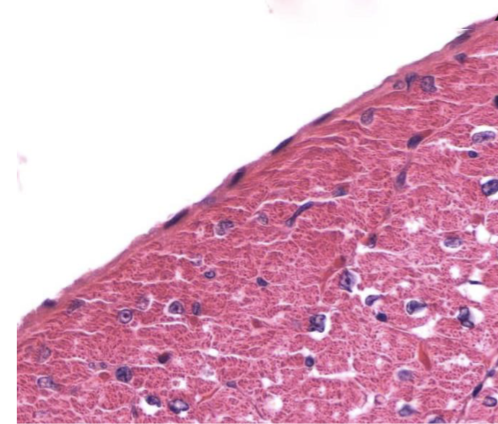

Identifique tipo de tejido conectivo

reticular

Indique sitio anatómico dónde se encuentra

higado